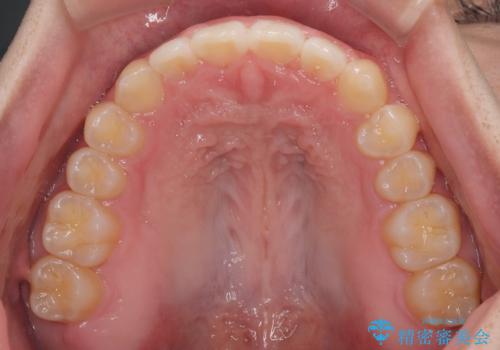

マウスピース矯正特有の奥歯への圧下により、一時的に噛みにくさを感じる場面もありましたが、

装着時間の調整と経過観察を行うことで症状は改善し、スムーズに治療を完了しました。